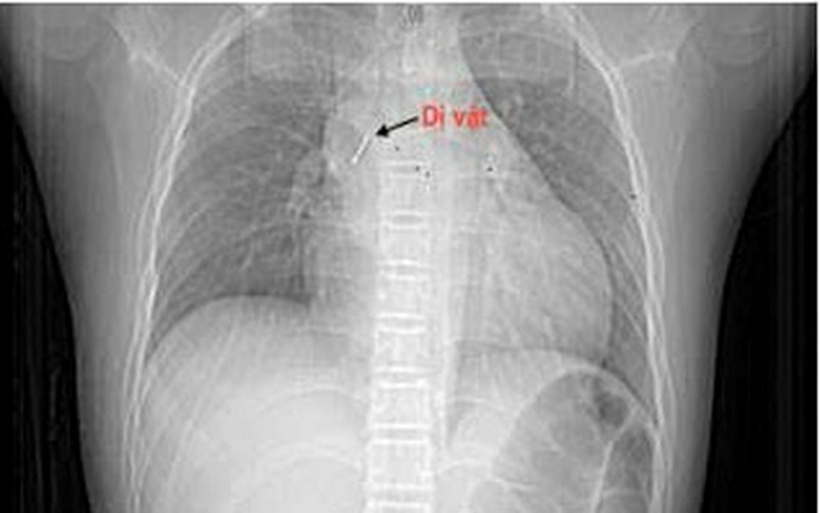

Theo gia đình bệnh nhi, vào tối ngày 13/10/2025, bé P.T.T.P (13 tuổi, Hà Nội) vừa ngồi xem điện thoại vừa ngậm chiếc đinh ghim bảng dài khoảng 2,5 cm. Trong lúc bé cười lớn, chiếc đinh bất ngờ rơi vào họng khiến bé ho sặc sụa, khó thở và cảm giác vướng ở ngực, nói khó. Gia đình hốt hoảng đưa trẻ tới bệnh viện gần nhà. Tại đây, bệnh nhi được làm các xét nghiệm máu, chụp phim cắt lớp vi tính lồng ngực, nội soi phế quản ống mềm, các bác sĩ xác định dị vật đã nằm sâu trong phế quản trung gian bên phải.

Dị vật trong đường thở bệnh nhi. Ảnh: Sức khỏe & Đời sống.

Do dị vật sắc nhọn, đâm xuyên thành phế quản gây chảy máu và phù nề niêm mạc nên việc gắp gặp rất nhiều khó khăn. Sau hơn 2 giờ thực hiện thủ thuật không thành công, bệnh nhi được chuyển khẩn cấp sang Bệnh viện Phổi Trung ương.